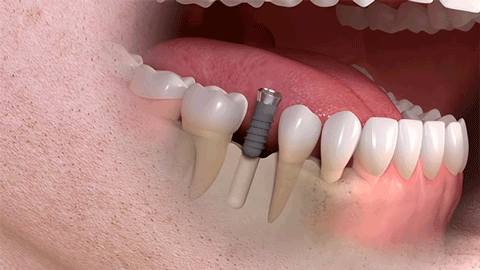

种植牙是医学界公认的理想修复方式,被誉为“人类的第三副牙”。相比活动假牙不舒服、难清洗、容易引起口腔黏膜病变,种植牙更稳固耐用,舒适美观,咀嚼功能好,一次种植,终生受用。种植牙不仅是中老年人的专利,年轻人因意外、牙病等造成牙齿缺失,也能够通过种植牙进行修复治疗,重获美丽笑容。

(单颗种植示例)